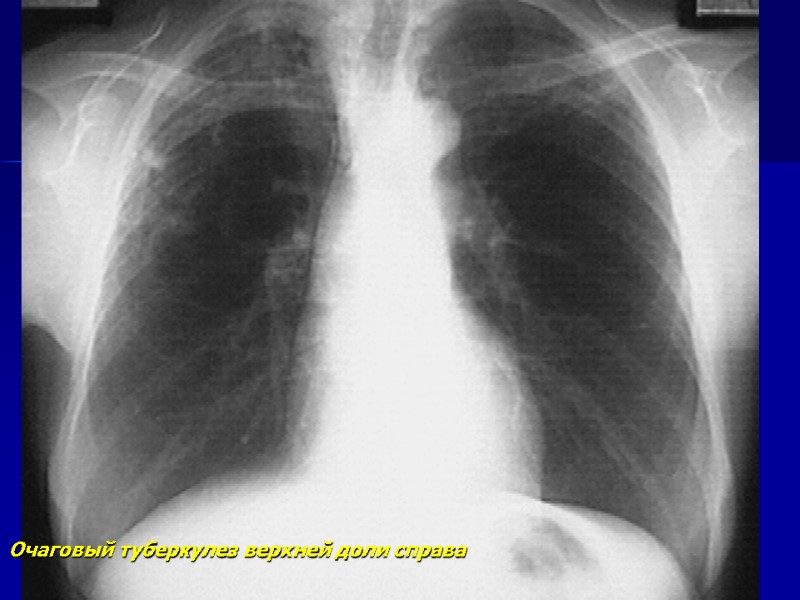

Очаговый туберкулез верхней доли справа

Очаговый туберкулез верхней доли справа (продолжение) через год